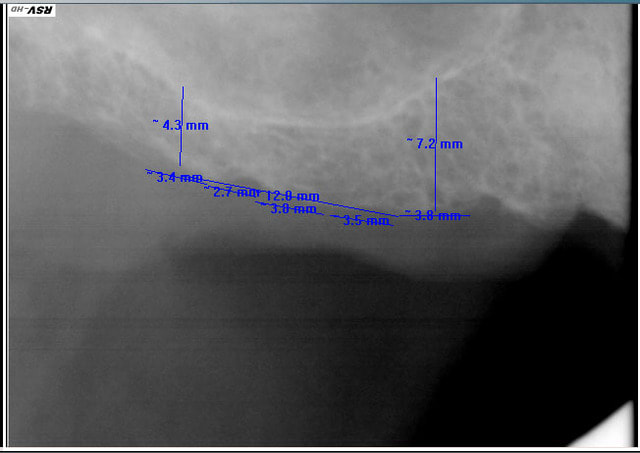

Comment traiteriez vous ce cas au maxillaire supérieur, secteur postérieur :

et surtout combien d'implants et en quelle position !

Il y a que des rvg, je sais, je sais il faut d'abord fr 1 examen endobuccal , type de gencive, HBD, ligne du sourire , occlusion etc...

Je lui ferai un cone beam s'il donne le feu vert sur le devis.

Pas compliqué : besoin de gagner plus de 2 mm sous le sinus? => sinus lift par voie latérale,

moins de 2mm ? => summers

Autre chose : tu ne peux pas mesurer sur une rétro-alvéolaire, il te faut impérativement un scan ou cone beam.

Même si l'imprécision n'est que d'1 mm, cela peut changer le plan de traitement.

Secteur droit: Sinus Lift pour dormir sereinement

-Secteur Gauche, ça peut se discuter:

I*2 et SL/Summers

Mais sans scan......